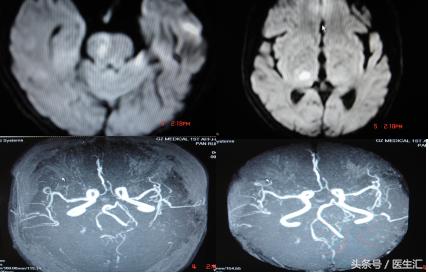

头颅MRI和MRA(图6)

专家判读:桥脑右侧半球后部,丘脑后部为实际梗死灶。大脑后动脉,一侧椎动脉显影不清。